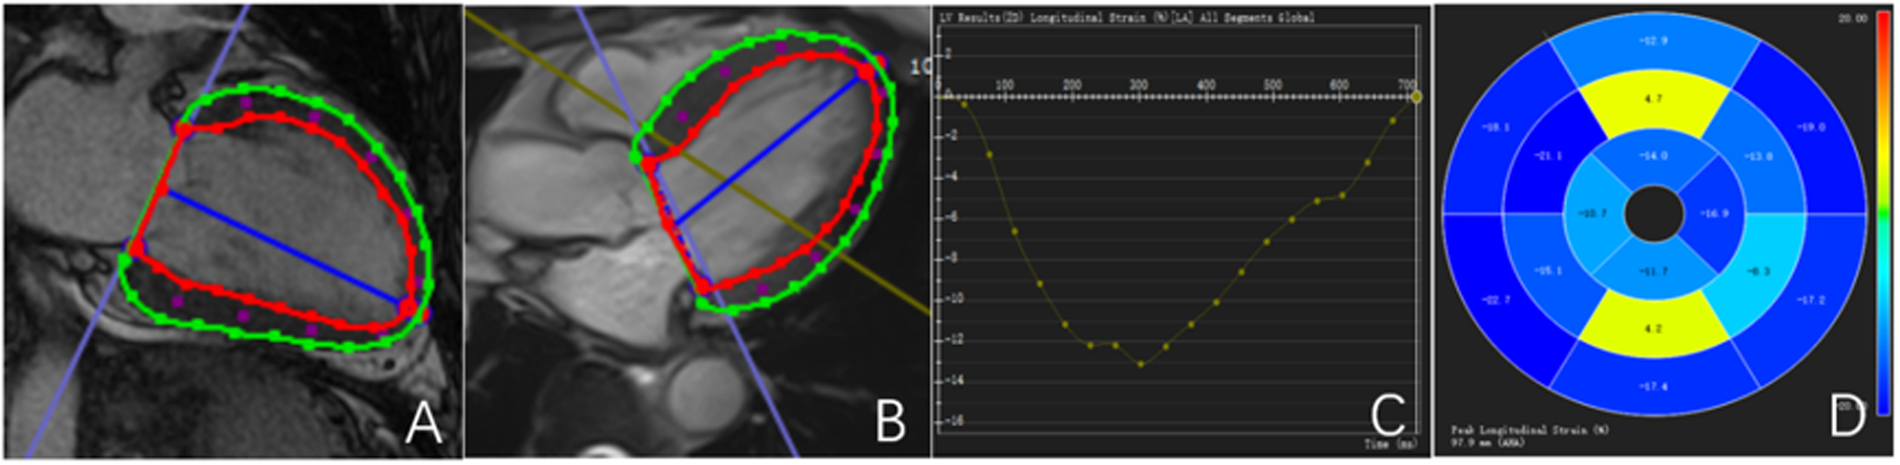

All CMR data were transferred to a dedicated workstation and analyzed using CVI 42 postprocessing software (version 5.6, Circle Cardiovascular Imaging Inc., Calgary, Alberta, Canada). Endocardial and epicardial contours of the left ventricle were manually traced at end-diastole and end-systole to calculate left ventricular ejection fraction (LVEF) and left ventricular myocardial mass (LVMM). Global myocardial deformation was evaluated using CMR tissue tracking (CMR-TT), with automatic voxel-based tracking throughout the cardiac cycle. Global radial strain (GRS), global circumferential strain (GCS), and global longitudinal strain (GLS) were measured, and corresponding strain curves and bull's-eye plots were generated (Figure 1).

Figure 1

Outline and description of myocardial strain. (A,B) Left ventricular endocardial and epicardial strain curves are delineated; (C) left ventricular GLS curve; (D) left ventricular GLS bull's-eye maps. The red line represents the contour of the endocardium.The green line represents the outline of the epicardium.The blue line represents the central axis of the left ventricular cavity.